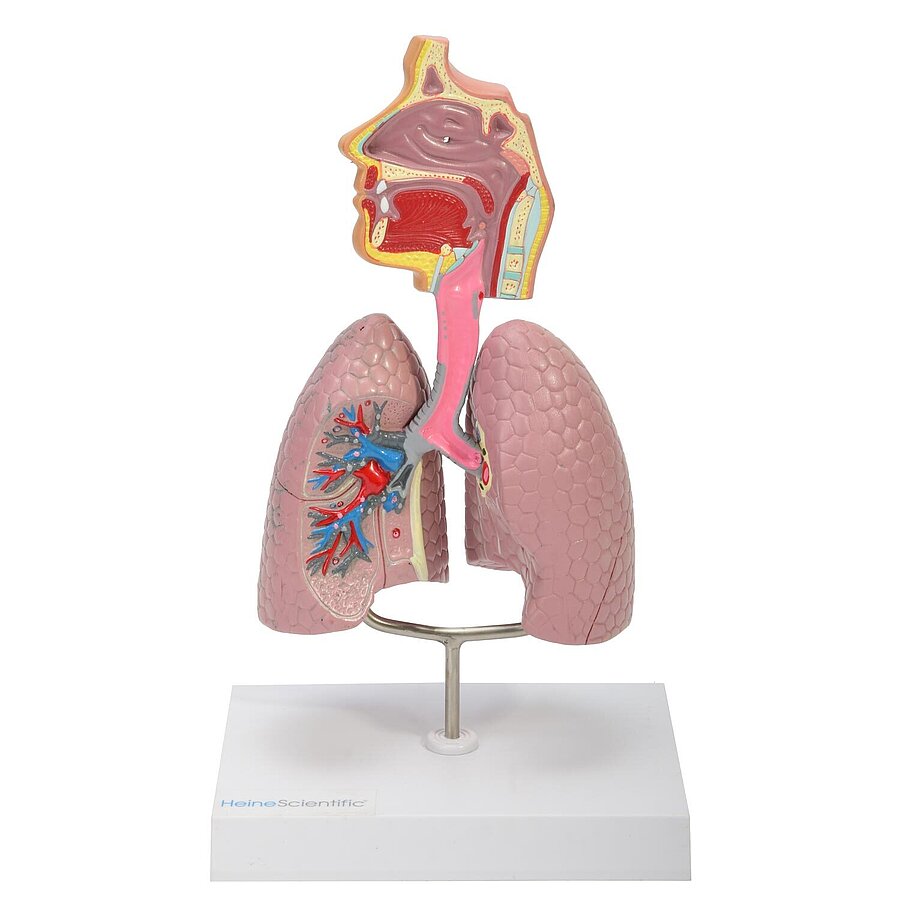

Atemwegsmodell

Präzise Nachbildung der Atemwege des Menschen

Perfekt für die Patientenaufklärung und das Medizinstudium

Auf einem Kunststoff-Sockel montiert, abnehmbar

Aufwändige Kolorierung

Maße: 27 x 16,5 x 12 cm (H x B x T)

Detaillierte Modelle für medizinische Ausbildungen

In unserem Sortiment finden Sie zahlreiche Modelle von HeineScientific sowohl für die Humanmedizin als auch für den Veterinärbereich. Hierzu zählen einzelne Körperteile, Organe, ganze Körperstrukturen oder Dentalmodelle. Mit ihrer Hilfe können Krankheiten und Funktionen nachvollzogen und gelehrt werden.